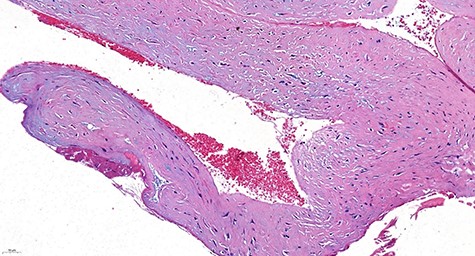

Microscopic examination of the surgical specimen demonstrated the presence of a cystic wall rimmed by paucicellular fibrocollagenic tissue, without evidence of an epithelial lining (Fig. 5).

Histologically, the wall of the cyst consisted of paucicellular connective fibrous tissue. No epithelial lining was evident (H&E stain, ×20).